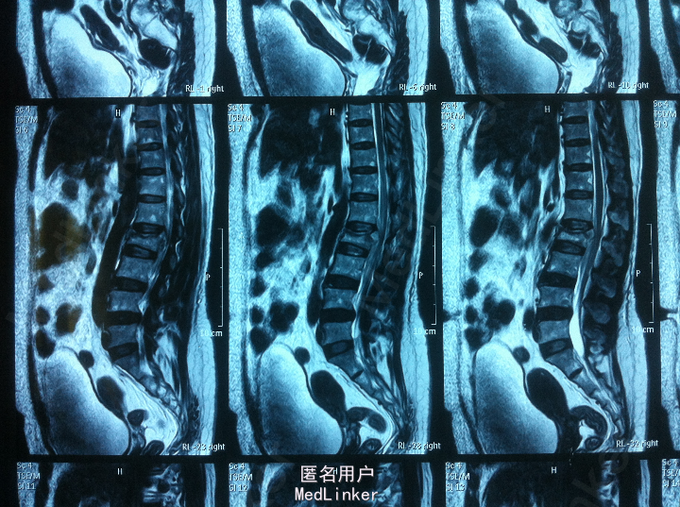

高处摔伤腰部疼痛、活动受限1入院。 中年女性,既往健康; 患者1天前从3米高处摔伤,臀部着地,及感腰部疼痛、活动受限,双下肢无放射性疼痛、麻木,双下肢活动可。

PE:腰部轻度后凸,叩痛,双下肢感觉无减退,双下肢肌力4-5级,巴氏征 阴性。 X-ray:腰2椎体骨折 CT:腰2椎体骨折,椎体后缘不连续 MR:腰2椎体骨折,腰2-3椎体水平硬膜外血肿

诊断:腰椎骨折 腰椎硬膜外血肿 处理:腰椎后路撑开复位内固定

术后1个月,患者轻度腰痛,双下肢感觉无减退,双下肢肌力5级 术后3个月,患者无明显腰痛,双下肢感觉、肌力正常 讨论:1、腰椎骨折累及中柱,无神经损伤表现,是否必须行椎板减压 2、外伤性硬膜外血肿,无神经损伤表现,是否有椎板减压指征